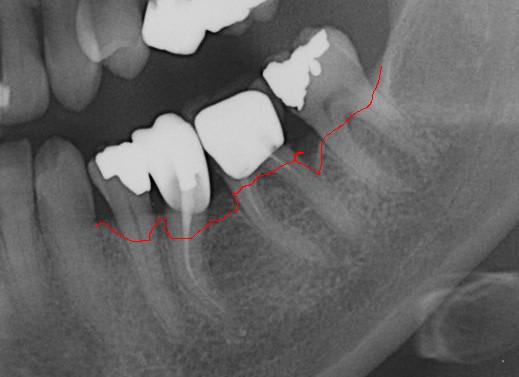

patiente 62 ans région Parisienne, appelle pour un avis, son praticien, paro, imlpanto etc... lui dit que sa paro n'a plus besoin de soin et propose pour les 6 antérieurs (j'ai le devis sous les yeux) 6 Inlay Core et 6 CCM...

Les panos sont du départ, les photos sont après un nettoyage ...profond et soins.

Empreinte, détourage et préparation des cires avec une occlusion différente de celle du wax up, un peu plus de DV

Le trait rouge sur les incisive donne à peu de chose prêt l'origine...